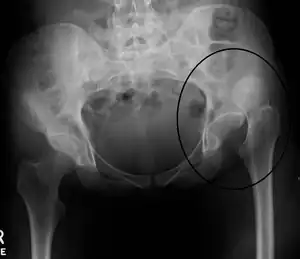

Anterior-posterior (AP) X-rays of the pelvis, AP and lateral views of the femur (knee included) are ordered for diagnosis.[13] The size of the head of the femur is then compared across both sides of the pelvis. The affected femoral head will appear larger if the dislocation is anterior, and smaller if posterior.[14] A CT scan may also be ordered to clarify the fracture pattern.

Hip dislocation -

Congenital hip dislocation -

Anterior dislocation of the hip -